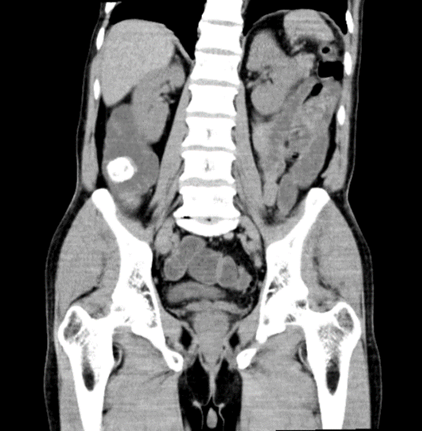

Ilustración 1 Tac con cálculo en válvula ileocecal

Fuente: Hospital de Especialidades Guayaquil “Doctor Abel Gilbert Pontón”.

Autor: Dr. Fernando Moncayo A.

Ilustración 2 Tac con cálculo en válvula ileocecal

Se presenta el caso de un paciente de sexo masculino, 68 años de edad, diabético, que debuta con dolor abdominal náuseas, vómitos, distensión abdominal intermitente con signo radiológico de obstrucción intestinal (edema interasas y signo de pilas de monedas), todos estos síntomas disminuyen luego de hidratación adecuada por lo cual se decide realizar tomografía computarizada la cual revela un cálculo de 2.5 a nivel de íleo terminal, por lo que se decide la intervención quirúrgica.